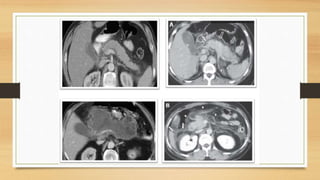

La TDM: c’est l’examen de référence. Elle devrait être effectuée au moins

48 heures après le début de douleurs, un examen trop précoce pouvant sous-

évaluer la gravité de la pancréatite. Une fois la pancréatite aiguë identifiée, la

TDM fait le diagnostic positif, élimine les diagnostics différentiels,

montre les complications potentielles, comme une nécrose du pancréas, ou

des collections nécrotiques.

Classification de BALTHAZAR

- Grade A : pancréas normal

- Grade B : hypertrophie diffuse ou localisée du pancréas

- Grade C : Inflammation limitée au pancréas et à la graisse péri-

pancréatique.

- Grade D : collection péri-pancréatique unique (coulée de nécrose)

- Grade E : phlegmon ou collections multiples et/ou présence de gaz intra

ou péri-pancréatique